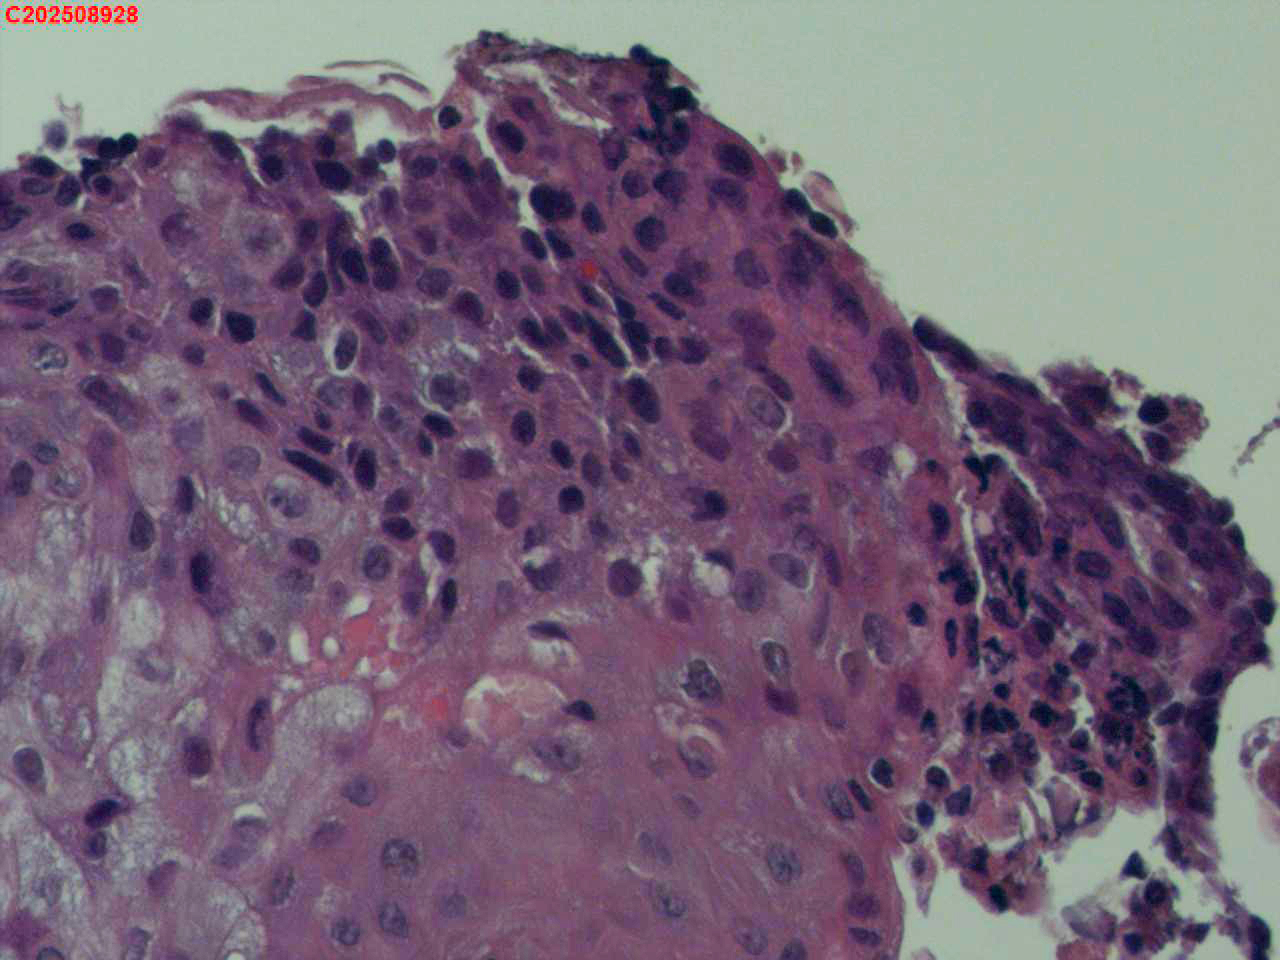

喉部右侧、声带下方咬检

男

56岁

喉Ca?

咳嗽

喉室内右侧声带下方新生物。

考虑鳞癌

鳞癌,有微浸润